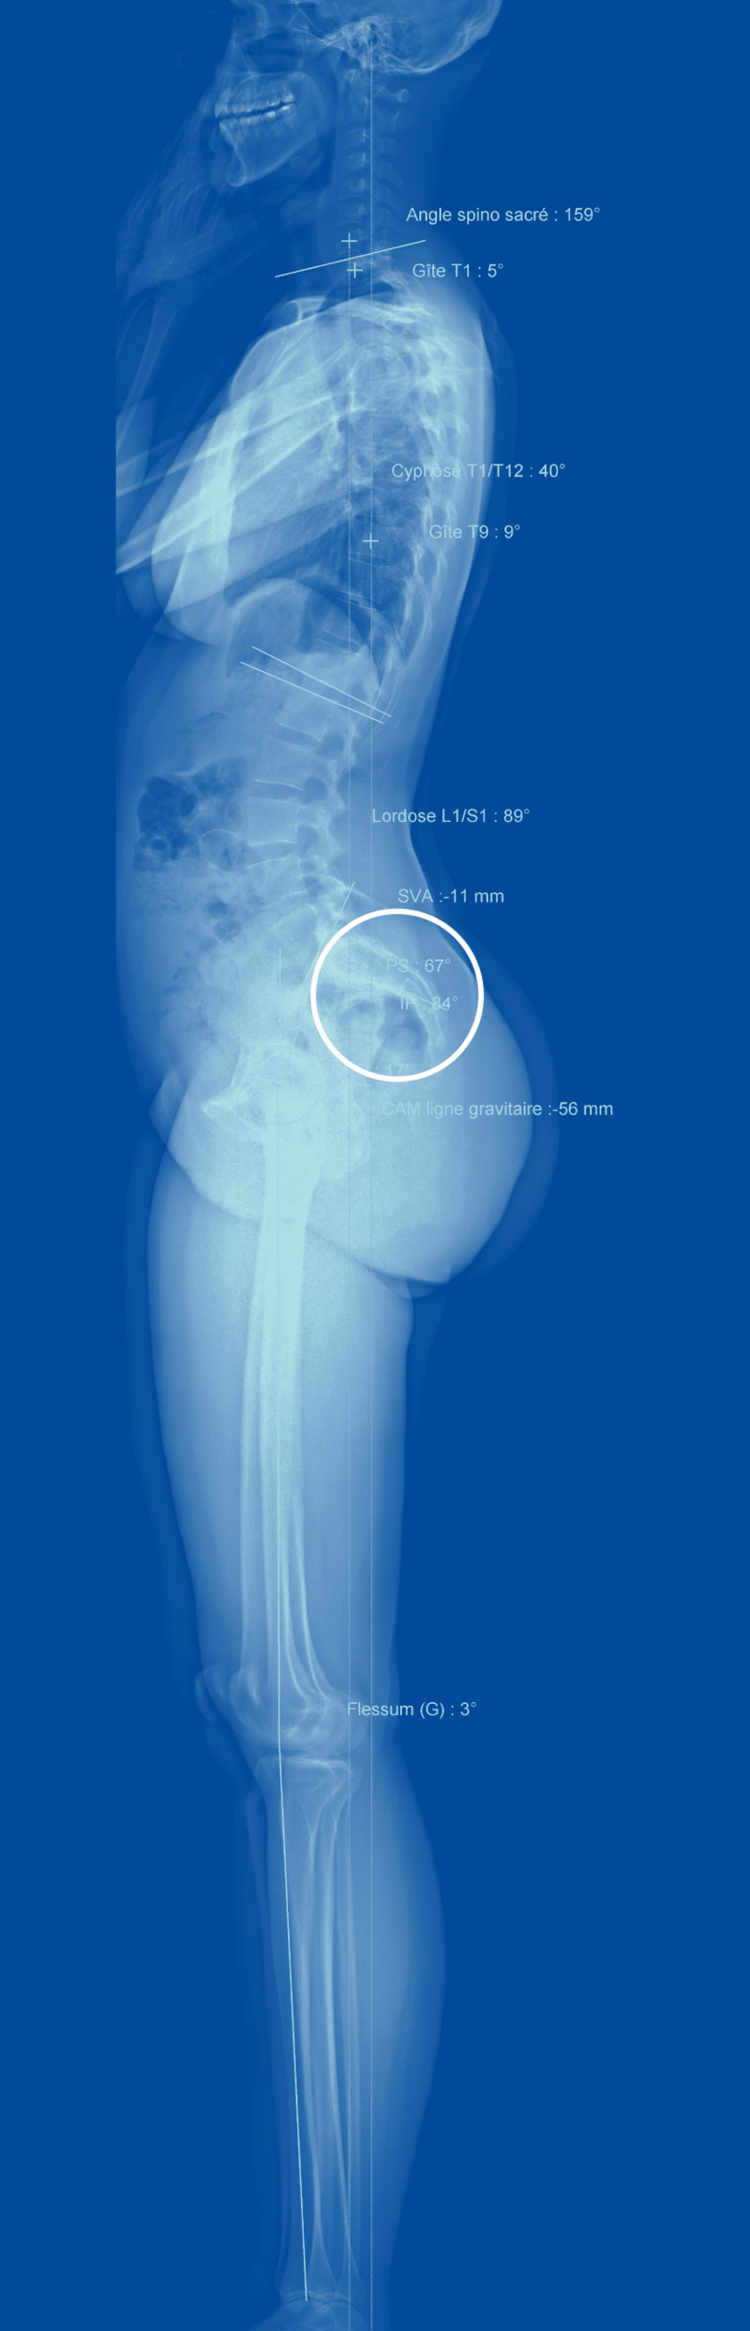

Mais l'EOS présente aussi des avantages par rapport à l'IRM et au scanner, explique Duccio Boscherini, neurochirurgien à La Source. Ces deux dispositifs fournissent en effet des images de la colonne, mais pas du reste du corps, contrairement à l’EOS. Or, les genoux ou les hanches peuvent être la cause de déséquilibres créant des maux de dos. De même, scanner et IRM sont réalisés quand la personne est couchée. «Ils fournissent donc des images restreintes de l'anatomie, dans une position statique et non physiologique.» Par opposition, l'EOS montre toute la personne en position debout.

Les médecins se rendent compte que les maux de dos doivent être évalués de manière globale, qu'ils sont le résultat d'une interaction subtile entre la posture de la personne, sa musculature et des caractéristiques anatomiques qui lui sont propres. «Il existe un cône d'économie en position debout, relate le chirurgien, un ensemble de postures possibles où la musculature est sollicitée au minimum.» Quand on s'en écarte, celle-ci doit travailler davantage, ce qui augmente le risque de maux de dos.

On a désormais identifié des paramètres normaux, poursuit le chirurgien, des angles (de cambrure par exemple) ou des mesures (l'emplacement du centre de gravité) qui permettent de prédire si une personne risque davantage de connaître des maux de dos. Telle patiente, par exemple, a un sacrum presque à l'horizontale, illustre le spécialiste: c'est très rare et cela cause naturellement une cambrure exagérée qui explique ses maux de dos.

Ces valeurs, l'EOS les calcule aisément et les fournit rapidement. Une fois munis de ces données, les spécialistes comprennent mieux l'origine des maux de dos. Ces mesures sont également précieuses pour déterminer où opérer pour être le plus efficace, de même que pour évaluer comment la colonne s'est repositionnée après une opération.